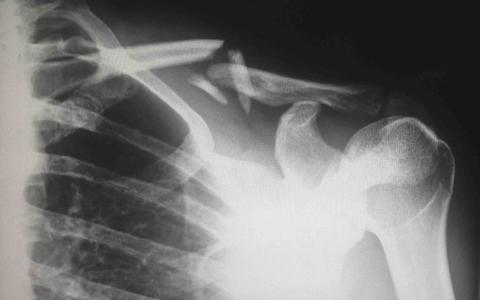

(image courtesy of Harlie Raethel)